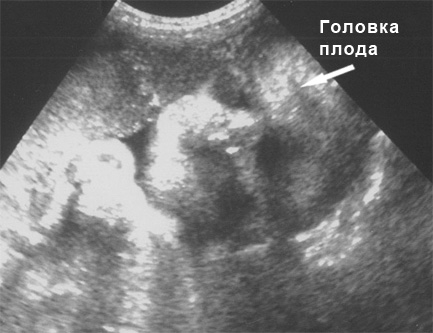

Фото плода на 35 неделе беременности (возраст плода 33 недели)

Вес и рост плода на 35 неделе беременности

К этому времени длина ребенка может составлять 47 см. Масса варьируется от 2500 до 2700 г. Объем живота составляет 92,4 мм, грудной клетки — 89,1 мм, а головы — 85,9 мм.

УЗИ на 35 неделе беременности

На 35-й неделе беременности плановое ультразвуковое исследование не предусмотрено. Оно проводится только при наличии определенных проблем. Одним из главных показаний для УЗИ на этом сроке является плацентарная недостаточность. Врач тщательно анализирует состояние плаценты и оценивает развитие малыша. В некоторых случаях может быть проведено доплеровское исследование сосудов.

Также важно обратить внимание на состояние околоплодных вод. Если в амниотической жидкости наблюдается крупнодисперсная взвесь, это может указывать на кислородное голодание плода.

Фото УЗИ на 35 неделе беременности